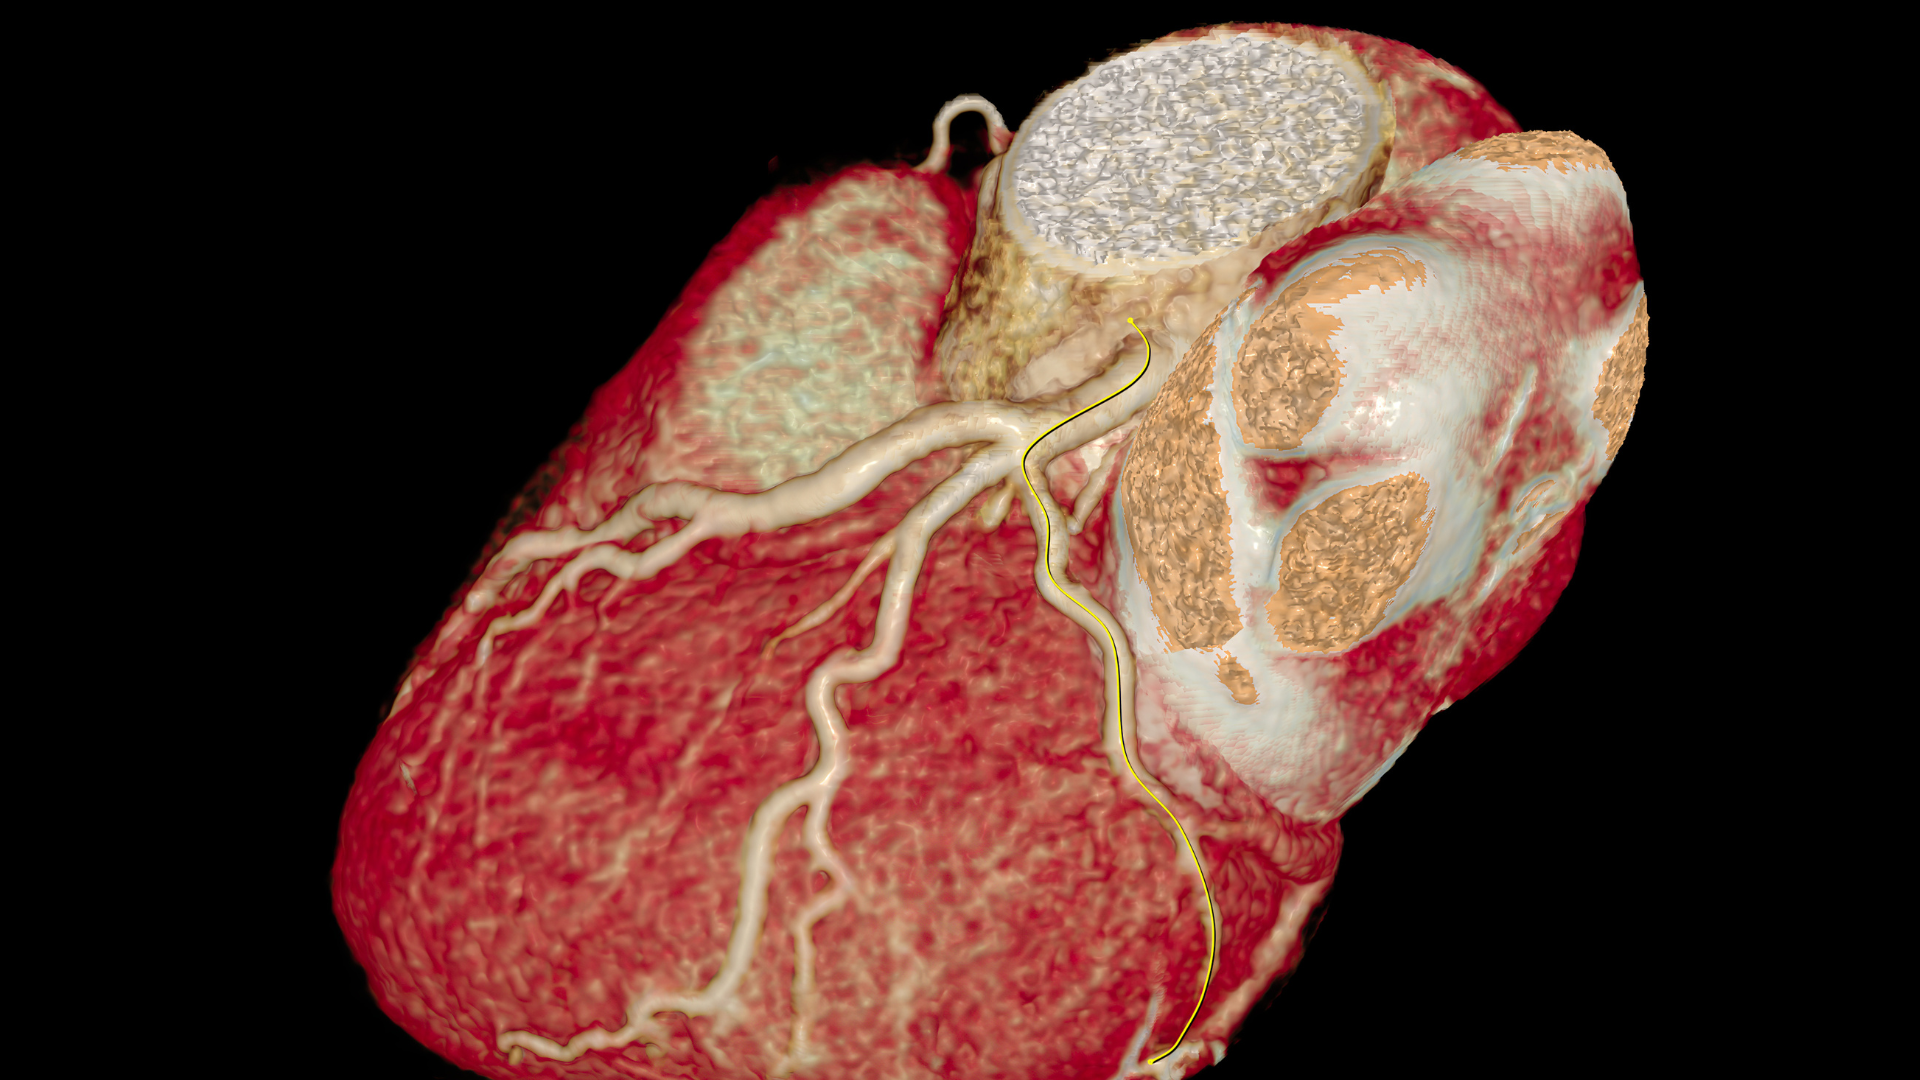

CT Coronary Angiogram

This test is a non-invasive way to assess heart arteries. The test has two parts. Firstly the test will provide a calcium score, a measure of the amount of calcium in the heart arteries, and will provide an indication of the severity of any disease of the heart arteries. Secondly some dye will be injected to assess any narrowing further. The images are very helpful in deciding if chest pain is caused by narrowing of the heart arteries. It also helps determine if risk factors (such as high cholesterol) are causing early changes, and helps decide if we need to be more aggressive in treating these risk factors.